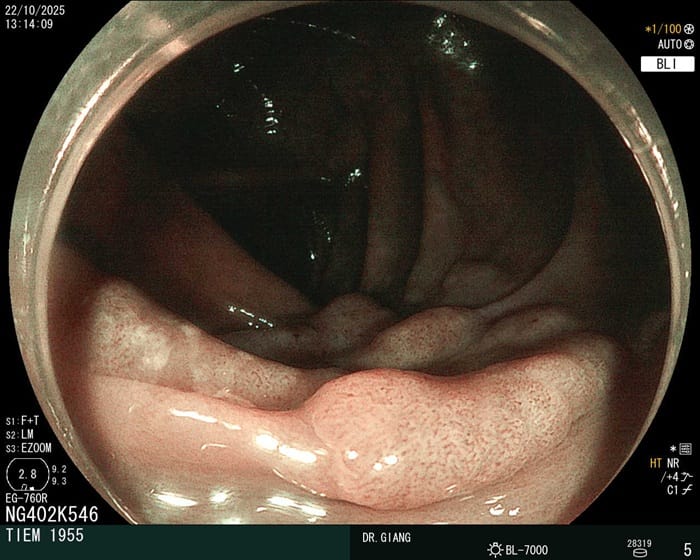

Hình ảnh niêm mạc đại tràng bình thường

Ở người bình thường, niêm mạc đại tràng có màu hồng nhạt, trơn láng, bề mặt sáng mịn và các nếp gấp đều nhau. Khi soi, không thấy vết loét, mảng trắng hay giả mạc, và ống đại tràng mềm mại, không co bóp bất thường. Đây là hình ảnh đặc trưng của một đại tràng khỏe mạnh, hoạt động ổn định.

Đại tràng bình thường, không có vết loét